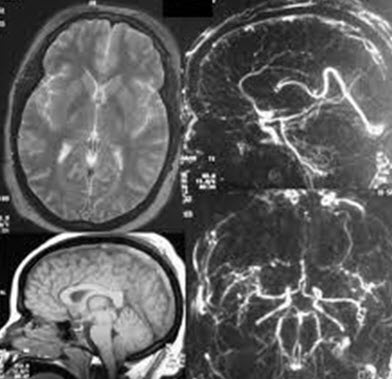

良性颅内高压症

图片尺寸272x240